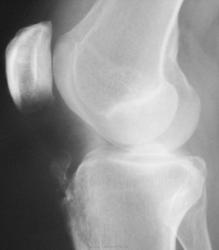

Случай №2 Женщина ,50 лет пришла на снимок коленных суставов на предмет ДОА. Снимки сделали. И у меня возник вопрос. На боковых снимках последствия болезни О.-Шлаттера? Или это обычное обызвесвление связок?

Случай №2. Это ещё называют тендинозом. Обызвествление связки надколенника. Причина: микротравмы.